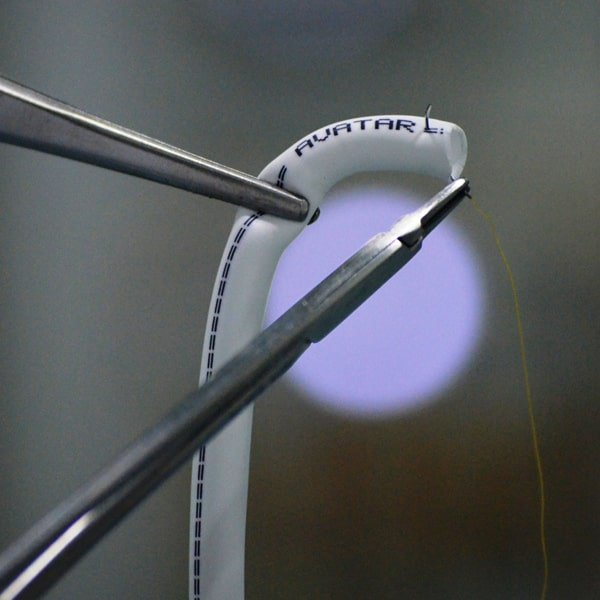

AVATAR® PTFE Vascular Grafts are made entirely from PTFE. The AVATAR® graft does not have an external wrap but instead has an open pore structure averaging 20 microns internodal distance, encouraging tissue ingrowth and making it soft and easy to suture.

AVATAR® PTFE Vascular Grafts are made entirely from PTFE. The AVATAR® graft does not have an external wrap but instead has an open pore structure averaging 20 microns internodal distance, encouraging tissue ingrowth and making it soft and easy to suture.

AVATAR® PTFE Vascular Grafts are made entirely from PTFE. The AVATAR® graft does not have an external wrap but instead has an open pore structure averaging 20 microns internodal distance, encouraging tissue ingrowth and making it soft and easy to suture. Helix grafts incorporate an external PTFE spiral support for use in applications where kink or crush resistance is required. Tapered and step tapered grafts can allow for better management of blood flow. All AVATAR® PTFE Vascular Grafts come sterile in dual barrier tray-within-tray packaging.